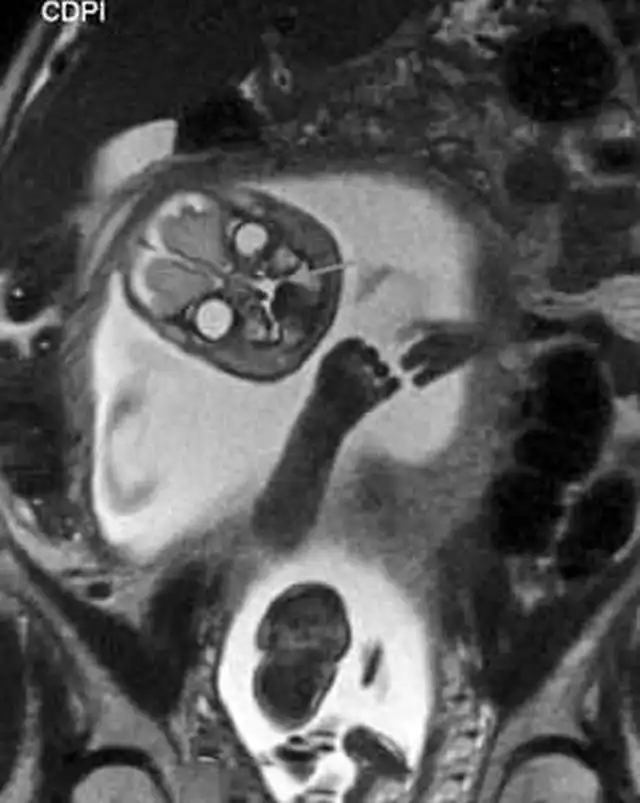

"Поздравляем, у вас демон": жуткий МРТ-снимок беременной женщины

Всегда подмечал в голливудских фильмах такое клише: беременной девушке делают УЗИ, а потом показывают матери и отцу эмбриончик, после чего все начинают умиляться, охать и обниматься, несмотря на то, что на экране по сути ничего не видно. В которой раз можно убедиться в том, что в мелодрамах правды нет. Это подтверждают жуткие МРТ-снимки беременной женщины из реальной жизни. Честно скажу, мне это сегодня приснится. Впечатлительным я бы рекомендовал не смотреть.